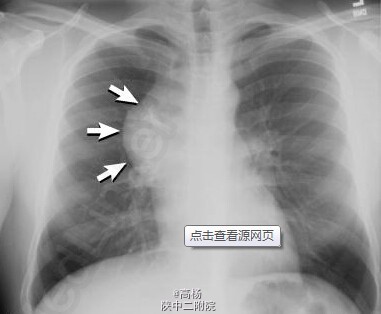

查体:口唇发绀,呼吸急促,吸气相呈轻度三凹症,右侧胸廓饱满,呼吸活动度减弱,听诊呼吸音减轻,叩诊呈实音,心音中,律齐。 辅查:胸片:右侧肺野密度增高影。CT:右侧胸腔混杂密度软组织肿块。如图。

诊断:右纵膈畸胎瘤 处理:予半高卧位,辅以吸氧、雾化、止咳等对症支持治疗。于全麻下行肿块切除术,选择右前外侧第六肋间切口进胸,膨肺探查右肺组织发育良好。术后称量肿瘤实性组织1.15kg。术后病理:肿瘤囊、实性共存,由成片皮肤、肠管、软骨、骨、神经组织及纤维脂肪组织构成。局部见少量实质尚未成熟的神经组织及腺管,但未见内胚窦,病理科建议可不予化疗,常规随访。术后予补液、营养支持等对症处理,病情稳定后出院。